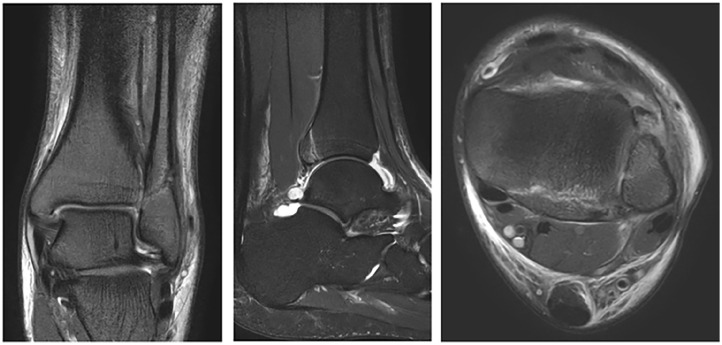

背景:踝关节骨折是一种常见的骨科损伤,其治疗主要取决于骨折的稳定性。Lauge-Hansen分类系统根据损伤机制和累及的韧带对骨折进行分类。旋后外旋(SER) 2型骨折对应于稳定的韦伯B型骨折,传统上采用非手术治疗,而SER 3和SER 4型骨折以联合破坏为特征,通常需要手术干预。我们假设一些表面稳定的损伤可能涉及额外的结构,挑战传统的治疗方法。本研究旨在确定影像学上稳定的SER 2骨折中SER 3和SER 4踝关节损伤的发生率。方法:该研究使用了黄金海岸医院和卫生服务(GCHHS)纵向队列的基线数据。在GCHHS骨折诊所就诊且SER 2骨折影像学稳定的患者被邀请参与研究。符合资格标准的患者接受踝关节磁共振成像(MRI)来评估关节联合韧带和踝关节韧带的完整性。结果:共招募56名参与者,女性38人(68%),男性18人(32%),平均年龄47.2岁。所有患者在x线评估中均有稳定的关节联合,并被诊断为稳定的SER 2踝关节骨折。MRI扫描显示,71% (n = 40)的SER 2损伤符合标准,25% (n = 14)的SER 3损伤伴胫腓后下韧带(PITFL)完全破裂,4% (n = 2)的SER 4损伤伴胫腓后下韧带(DL)破裂。这些结果挑战了影像学上稳定的SER - 2骨折在所涉及的其他结构方面始终稳定的假设。结论:该研究强调了相当一部分看似稳定的踝关节骨折涉及的结构比以前认为的更多。这表明SER 3和SER 4损伤的处理可以包括非手术治疗。证据等级:III级,队列研究。

Background: Ankle fractures are common orthopaedic injuries, and their management is primarily determined by fracture stability. The Lauge-Hansen classification system categorizes fractures according to mechanism of injury and ligaments involved. Supination external rotation (SER) type 2 fractures correspond to stable weber B fractures and are traditionally treated nonoperatively, whereas SER 3 and SER 4 fractures, characterized by syndesmosis disruption, typically require surgical intervention. We hypothesize that some apparently stable injuries may involve additional structures, challenging the conventional treatment approach. This study aims to determine the prevalence of SER 3 and SER 4 ankle injuries among radiographically stable SER 2 fractures.

Method: The study used baseline data from a longitudinal cohort conducted at Gold Coast Hospital and Health Service (GCHHS). Patients attending the GCHHS fracture clinic with radiographically stable SER 2 fractures were invited to participate. Those meeting the eligibility criteria underwent ankle magnetic resonance imaging (MRI) to evaluate the integrity of syndesmotic and ankle ligaments.

Results: Fifty-six participants were recruited, 38 (68%) female and 18 (32%) male, with a mean age of 47.2 years. All had stable syndesmoses on radiographic assessment and diagnosed with stable SER 2 ankle fractures. MRI scans revealed that 71% (n = 40) met the criteria for SER 2 injuries, 25% (n = 14) for SER 3 injuries with complete ruptures of posterior inferior tibiofibular ligament (PITFL), and 4% (n = 2) for SER 4 injuries with PITFL and deltoid ligament (DL) ruptures. These results challenge the assumption that radiographically stable SER 2 fractures are consistently stable in terms of additional structures involved.

Conclusion: The study highlights that a considerable proportion of seemingly stable ankle fractures involve more structures than previously thought. This suggests the management of SER 3 and SER 4 injuries could include nonoperative treatment.